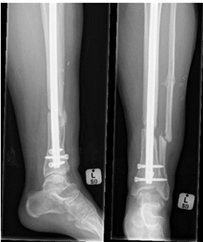

There were 61 males (61%) and 39 females (39%). The median age of the participants was 36 (47-27) years, ranging from 18 to 77 years. A total of 80 patients (80.0%) were treated with intramedullary nailing, 20 (20.0%) treated with plating. In the plated group, 15 were treated with anterolateral plates (75%) and five treated with medial plates (25%). Five of the plate cases were more distal and comminuted and not amenable to intramedullary nailing. The immediate post-operative AP X-Ray views showed that 73 participants had an acceptable alignment (73%) and 27 had malalignment (27%) (Figure 3 & 4). Lateral view showed that 98 participants had acceptable alignment, with unacceptable alignment in only two patients.

Figure 3 Malunion post IMN.

Figure 4 Malunion post IMN.